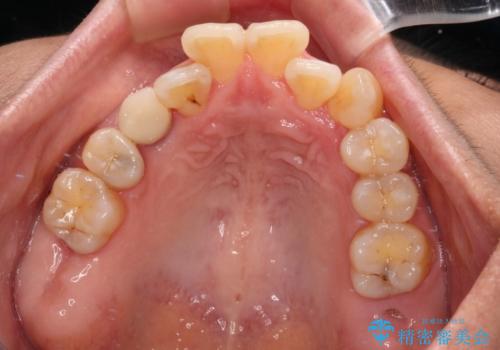

崩壊した歯は全て抜去し、他人から見える位置の歯はセラミッククラウンが装着され、整った口腔環境となりました。